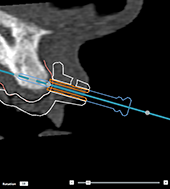

Anchor

pins and dental scan (partially edentulous workflow)

When using a

smart-fused surface scan, the sleeve must be placed close to the mucosa

(0.5 to 1 mm distance from the mucosa, represented through the surface

scan) but should not protrude beyond the smart-fused surface scan.

|

Correct |

|

Incorrect: the anchor pin sleeve

protrudes through the dental scan (soft tissue) and the template

will not fit into the patient’s mouth. |